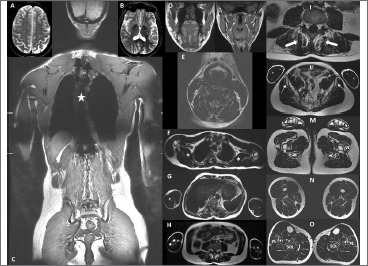

Tubular aggregate myopathy is a rare neuromuscular condition associated with the presence of myofibers protein accumulations, in the form of dense tubular aggregates. Clinically it is characterized by proximal muscular weakness, exercise-induced cramps, myalgias, and ocular features such as ophthalmoplegia and pupillary abnormalities. The involvement of the central nervous system is rare and not completely elucidated. Variants in STIM1, ORAI1, CASQ1 genes are frequently associated with tubular aggregate myopathy. Here we describe a 35-year-old man who presented neonatal hypotonia, motor delay, seizures, and sensorineural hearing loss. During a SARS-CoV-2 infection at the age of 35, he developed myoclonus, encephalopathy, and marked muscular weakness. A deltoid muscle biopsy revealed the presence of tubular aggregates. Genetic analyses including a Whole Genome sequencing failed to reveal a genetic cause. In conclusion, we enlarge the clinical spectrum of tubular aggregate myopathy associated with central nervous system involvement.